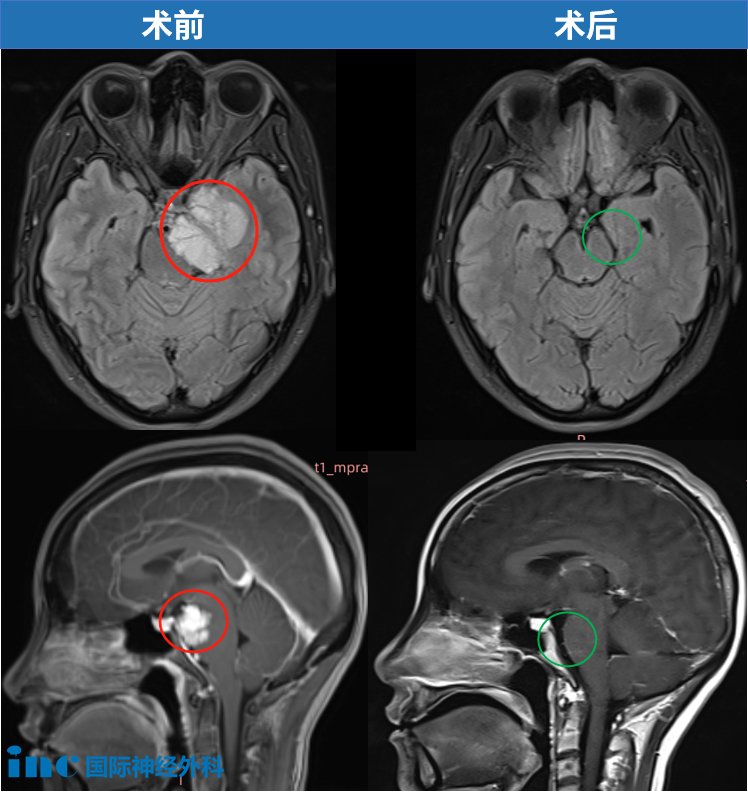

36岁的小宛、岩尖区4.5cm脑膜瘤,视力下降

在北京天坛医院,福教授精湛的手术操作下,肿瘤顺利切除。点击阅读:天坛医院手术纪实 | 4.5cm脑膜瘤紧压脑干成功手术,勇敢辣妈的彪悍人生!

54岁男性、岩斜区脑膜瘤、吞咽困难,肿瘤显著增大、压迫脑干

福教授采用了联合岩骨入路的方法,成功地对肿瘤进行了手术切除。点击阅读:良性脑瘤能长多快?这脑膜瘤每年长2.38cm³,还能“挤扁”脑干!

70岁女性、岩斜区脑膜瘤,脸部剧痛,伴幕上侵犯,可见脑干受压现象,肿瘤延伸至梅克尔腔(Meckel’s cave)及右侧海绵窦。

福教授采用了微型联合岩骨入路(mini-CTPA),成功实现了肿瘤的近全切除。点击阅读:【福医妙手】INC国际教授福洛里希脑膜瘤案例九|70岁,岩斜区脑膜瘤,近全切